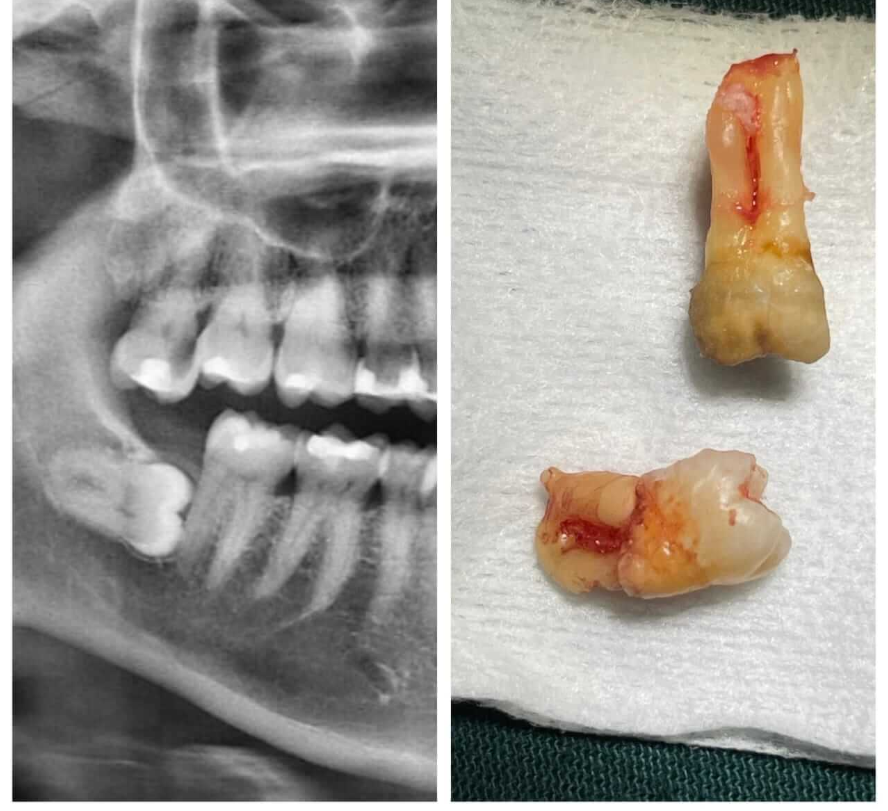

Horizontal impaction identified on X-ray and successful post-extraction result.

Impacted wisdom tooth safely removed with precise surgical planning and fast recovery.